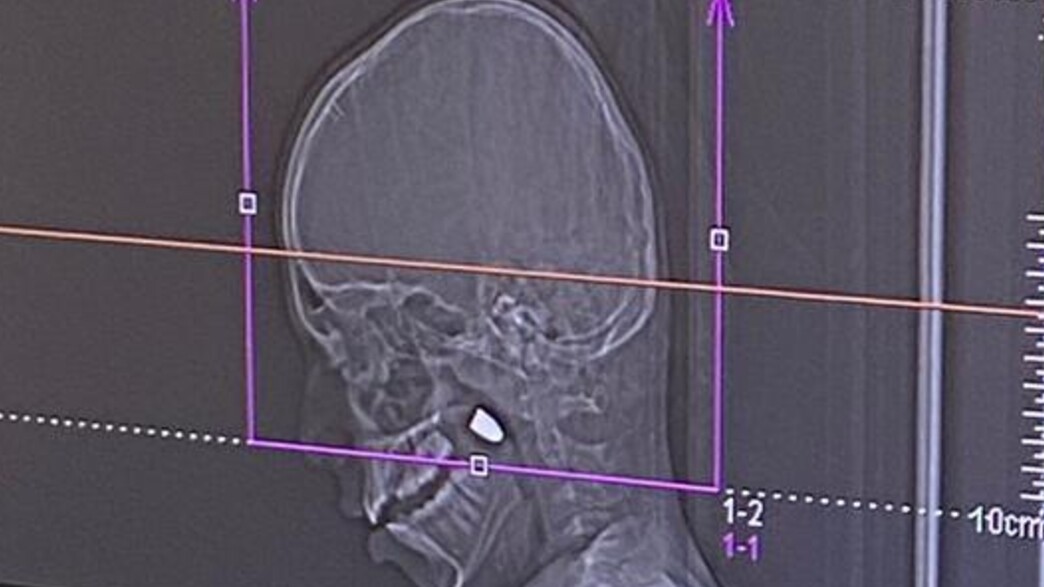

"פתאום הילד יורד למטה", הוא משחזר. "בן דוד שלו אומר לו: 'יורד לך דם מהראש'. ראינו חור קטן כזה, קצת דם. שאלנו אותו איפה קיבלת מכה, והוא אומר שהוא לא יודע". לידינו הגיע צילום הרנטגן של בן ה-11 שבו נראה הקליע בתוך ראשו.

אבל כשהילד החל להקיא, התקבלה ההחלטה לפנות אותו בדחיפות לבית החולים פוריה. שם הגיעה הבשורה הקשה באמת. "עשו לו סי-טי, ואז אמרו לנו שיש לו קליע בתוך הראש", מספר ואליד את ההפתעה שאחזה בו. "זה נכנס מהצד השמאלי ונתקע בלסת".